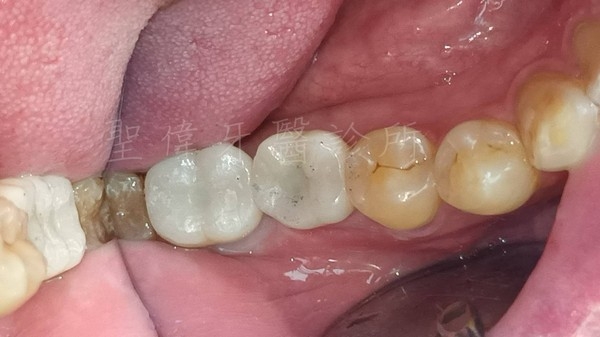

在聖偉牙醫診所植牙效果自然,大推林子揚院長!

終於在聖偉牙醫診所植牙,把缺牙的牙齒補上